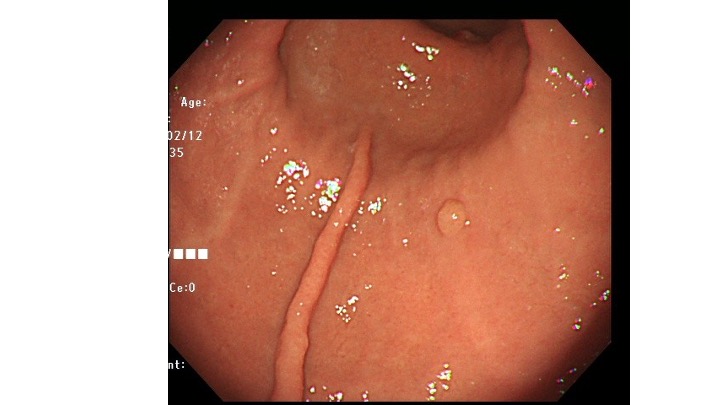

今回提示する症例(ピロリ除菌後)は、隆起型の早期胃癌で、表層に癌の露出を認めない早期胃癌です。

胃内には複数の胃底腺ポリープが散見されます。良性で取る必要のないポリープです。

前庭部の隆起は、良性ポリープではなく、癌疑いで生検しましたが、結果は Group1の結果でした。